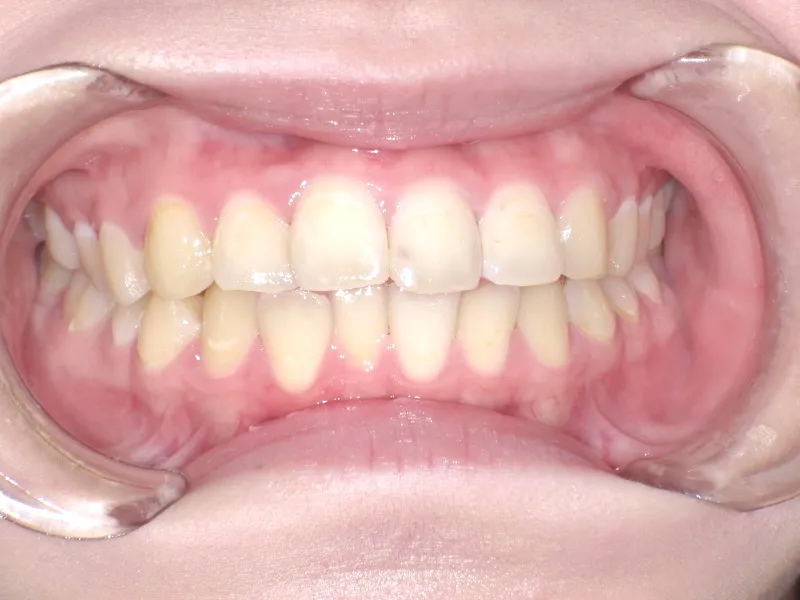

初診時年齢 19~29歳 (女性) 主訴 上下がガタガタ・出っ歯

診断名 叢生・上下顎前突 装置名

上下の歯並びがガタガタで口元が出ています。

再治療の時は、上の歯は前から見えにくいオリジナル固定装置、下の歯はマルチブラケット装置を使用し、治療しました。

治療回数62回、1年6ヶ月の治療期間で矯正治療を終了しました。

前回の治療で歯の根っこの部分の位置を治していたので、全部前から付けるのではなく最低限見える装置で治せました。

一度治療して、後戻りでお困りの場合のご相談もお待ちしております。